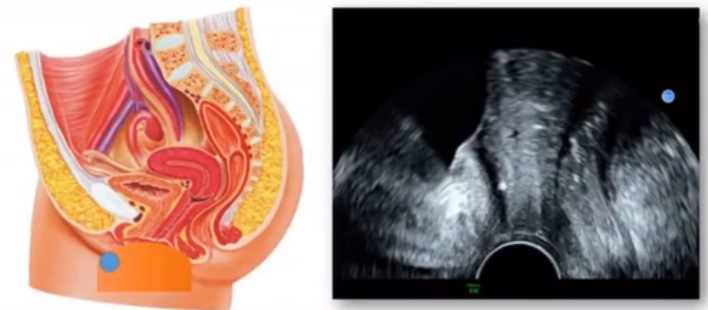

位于輸卵管的后下方,子宮兩側(cè)的后上方;借卵巢系膜與子宮闊韌帶后層相連。正常成人卵巢約4x3x2cm,跟睪丸的數(shù)值差不多,都是性器官,絕經(jīng)后卵巢萎縮變小、變硬。所以絕經(jīng)后婦女很難找到卵巢,主要功能:生殖和內(nèi)分泌功能分泌性激素。女性的第二性征。女性?xún)?nèi)生殖器的血管分布,動(dòng)脈有子宮動(dòng)脈,卵巢動(dòng)脈,陰道動(dòng)脈,陰部?jī)?nèi)動(dòng)脈。靜脈它是與動(dòng)脈伴行。重要了解的是子宮動(dòng)脈,子宮動(dòng)脈是髂內(nèi)動(dòng)脈前干的重要分支,妊娠時(shí)候血流速度會(huì)增加的,為無(wú)創(chuàng)性檢查胎盤(pán)血管阻力的方法。未孕期頻譜為高阻力低舒張波形;正常妊娠時(shí)血流速度增加,血流阻力下降。